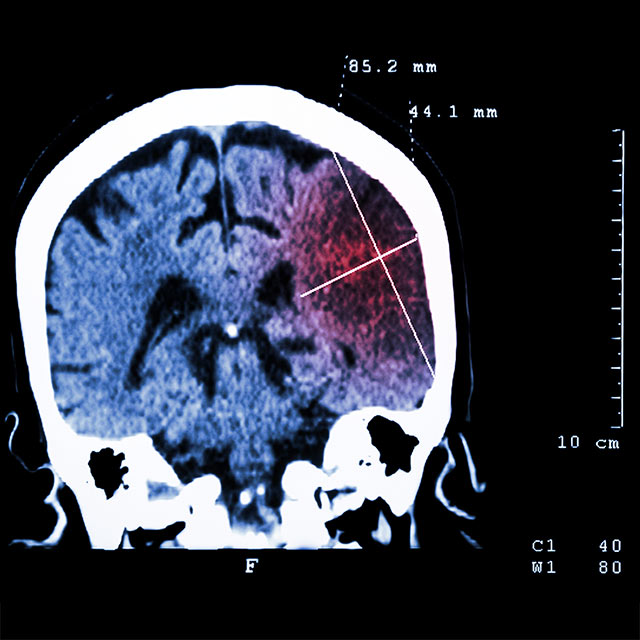

Ruoli’s research interests include hypoxia biology, stroke medicine and blood brain barriers. In particular, his work focuses on pharmacological activation of hypoxia inducible factor pathways in stroke therapy and prevention.